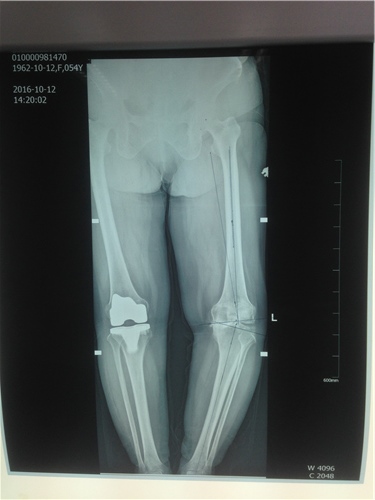

患者王某,女,54岁,合阳县人。二十余年前,出现左膝关节疼痛、肿胀,严重影响日常活动,稍微休息后感到缓解,但疼痛的症状时常发作,而且越来越重。为明确病情前来我院,在门诊检查后,诊断为膝关节骨性关节炎,由骨二科收住院。

患者曾在2015年因右膝关节重度骨性关节炎,在西安行右全膝关节置换术。住入我院后,骨二科副主任医师胡洪波为患者做了详细全面的检查,最终诊断为左膝关节骨性关节炎IV期,右全膝关节置换术后,高血压病3级。因为患者左膝关节的疼痛,导致走路不稳,影响到了日常生活,已经达到了手术指征,骨二科医师在经过和患者及家属的反复沟通后,决定为患者实施左侧全膝关节表面置换术。

10月15日,由胡洪波主刀,为患者施左膝关节骨性关节炎全膝关节表面置换术,手术过程顺利。术后2天患者开始屈膝运动训练及肌力训练,3天即可扶支柱下床行走,术后7天出院,术中患者的膝关节畸形也成功纠正,目前患者膝关节功能良好,行动无阻碍。